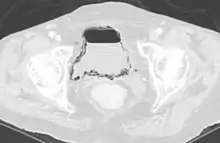

| Emphysematous cystitis in computertomography | |

Diagnosis is made by patient history of passing air or a sputtering urine stream. CT scans may show air in the urinary bladder or bladder walls.